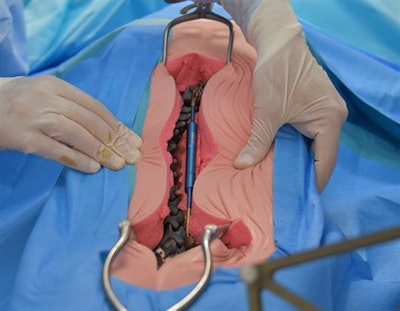

The 3D-printed model of the spine. All image courtesy of Amiens-Picardie University Hospital.A major component of the preparation included practicing the new surgery, which the physicians accomplished using 3D printing. First, the group created a 3D reconstruction of the child's chest cavity, and then they used that information to print an exact replica of the patient's spine at the SimUSanté training center affiliated with the hospital. Finally, they situated the resulting 3D-printed spine model into a mannequin the same size as the child.